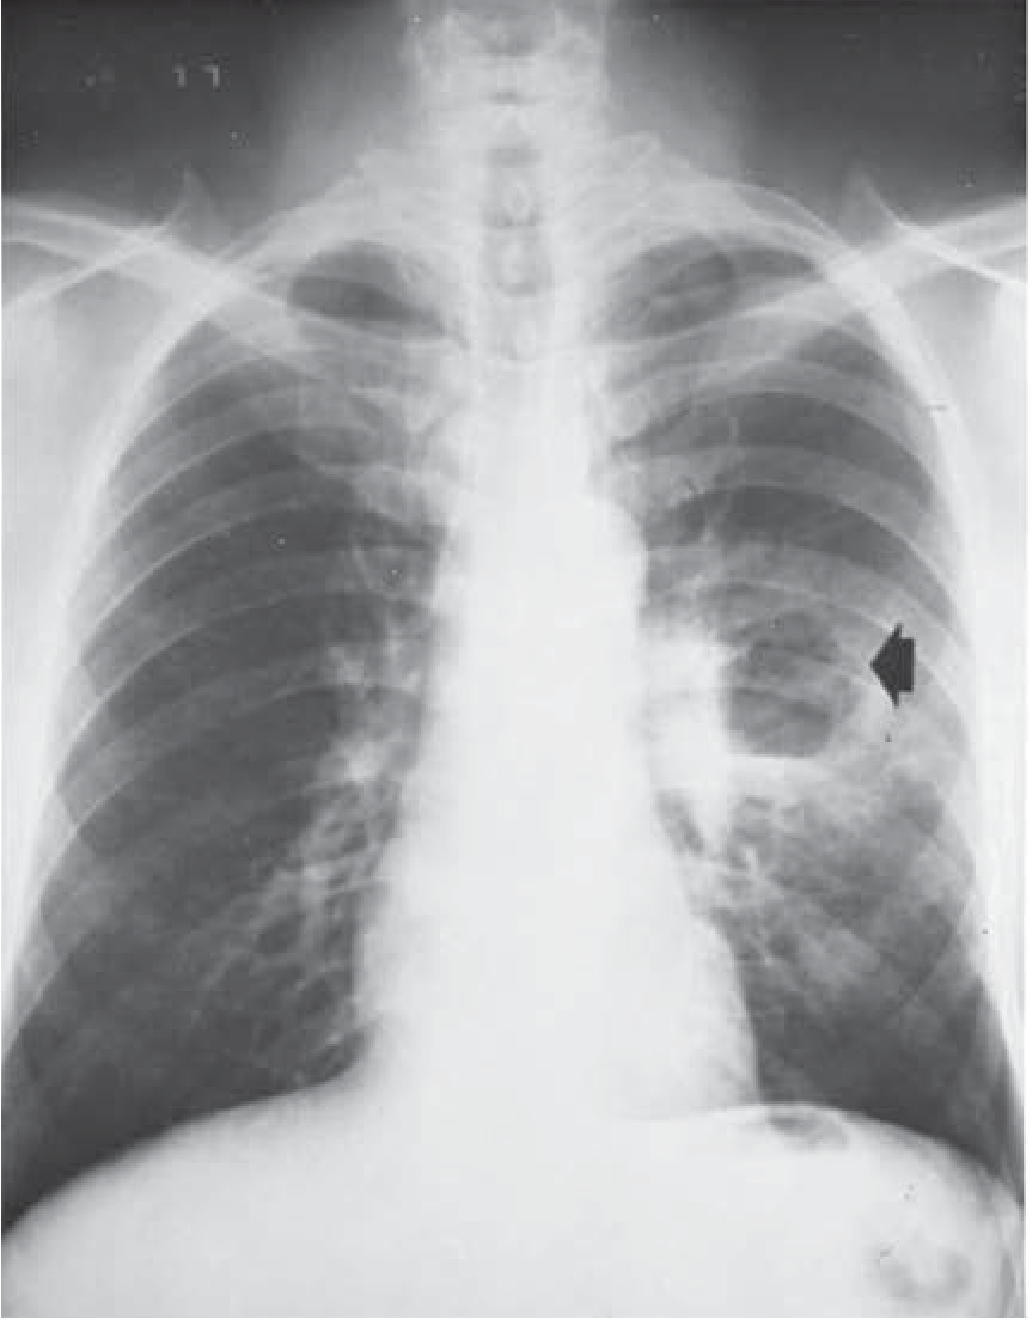

Lung abscess: chest X-ray showing cavity in left upper lobe with air-fluid level

CXR: lung abscess cavity with air-fluid level (arrow) in the left upper lobe — Schwartz's, p. 735